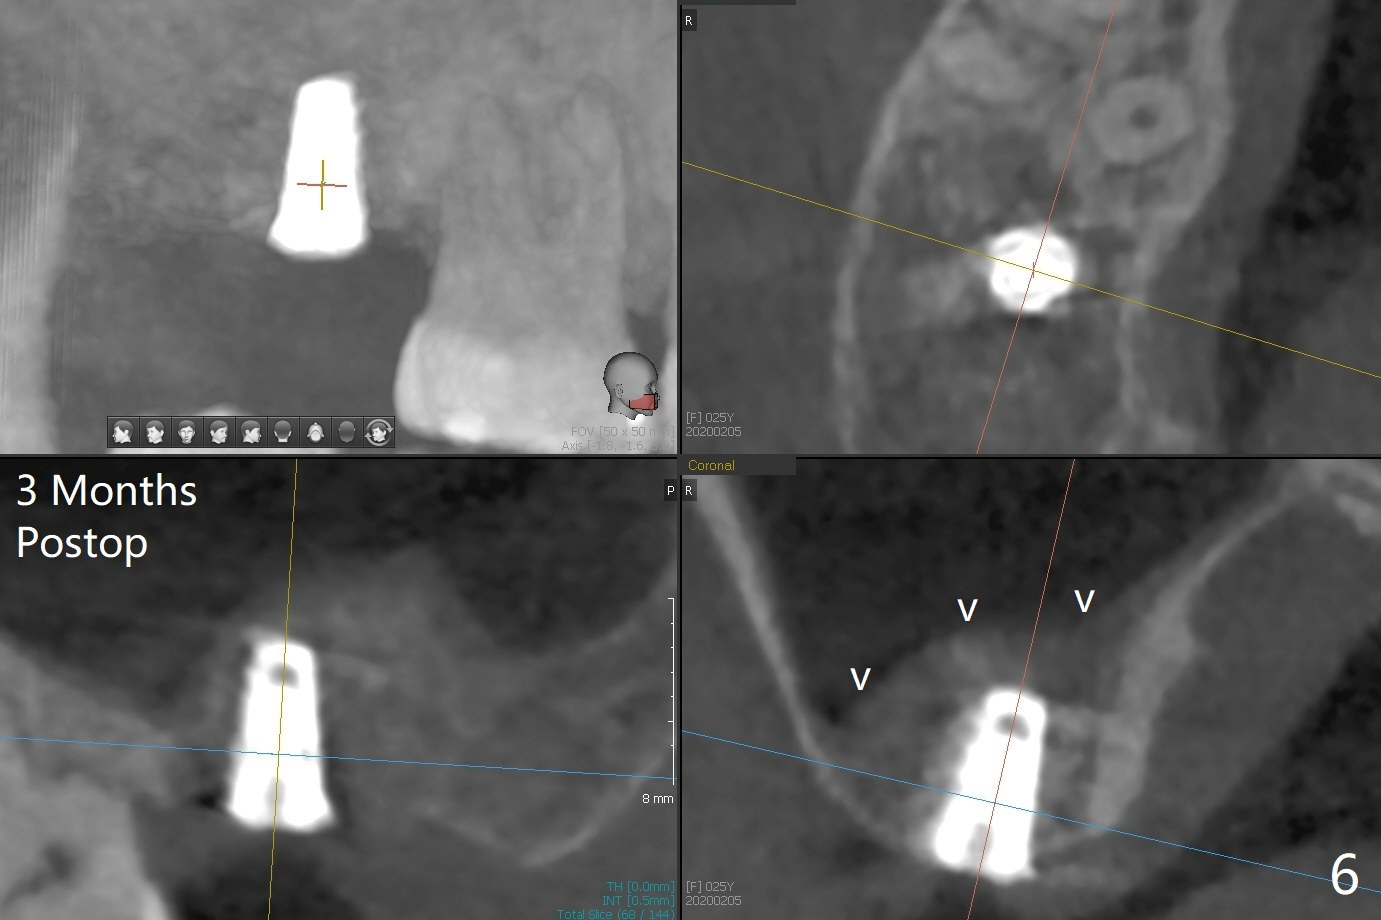

With 4-5 mm remaining bone at #2, the initial osteotomy is 4.0x3.5 mm with regular drills with sharp end. After using 3.6 mm sinus drill with round end for ~ 4 mm in depth, water lifting is conducted smoothly. After use of the same safe drill for ~ 5 mm, water lifting is done. Nose blowing indicates possible sinus membrane perforation. With insertion of collagen plug (PRF is not prepared because of thin vein), mixture of autogenous bone and allograft is lifted with 4x9 mm dummy implant with a guide (Fig.1 G). With placement of more of bone graft, a 4.5x7 mm definitive implant is placed with ~ 25 Ncm (Fig.2). Although bone graft around the implant is limited (Fig.3,4 *), the sinus membrane is lifted (in fact expanded by water) substantially (arrowheads, as compared to preop CT). The healing abutment is dislodged 1 month postop. Before impression, use sensor 1 to take PA to determine whether the abutment contacts the crestal bone or not. Take 5x5 cm CT for sinus membrane thickness. Although the bone graft surrounds the implant 3 months postop, the implant is tender when a 4.5x4(2) mm cemented abutment is being placed (Fig.5). Later a healing screw is placed (Fig.6,7). The sinus membrane has shrunk (arrowheads). Progressive loading is mandatory. The implant is uncovered with a 6x2 mm healing abutment 6.5 months postop (Fig.8). A 5.5x4(2) mm pair abutment is placed and torqued at ~20 Ncm with mild tenderness 7 months postop (Fig.9 BW). A provisional is fabricated for progressive loading because of mild crestal bone loss (*). The abutment is able to be torqued at 35 Ncm 9 months postop. Impression is taken. Return to Upper Molar Immediate Implant Trajectory II 18 Next Case with 3-4 mm Bone Screw Xin Wei, DDS, PhD, MS 1st edition 10/29/2019, last revision 02/23/2021